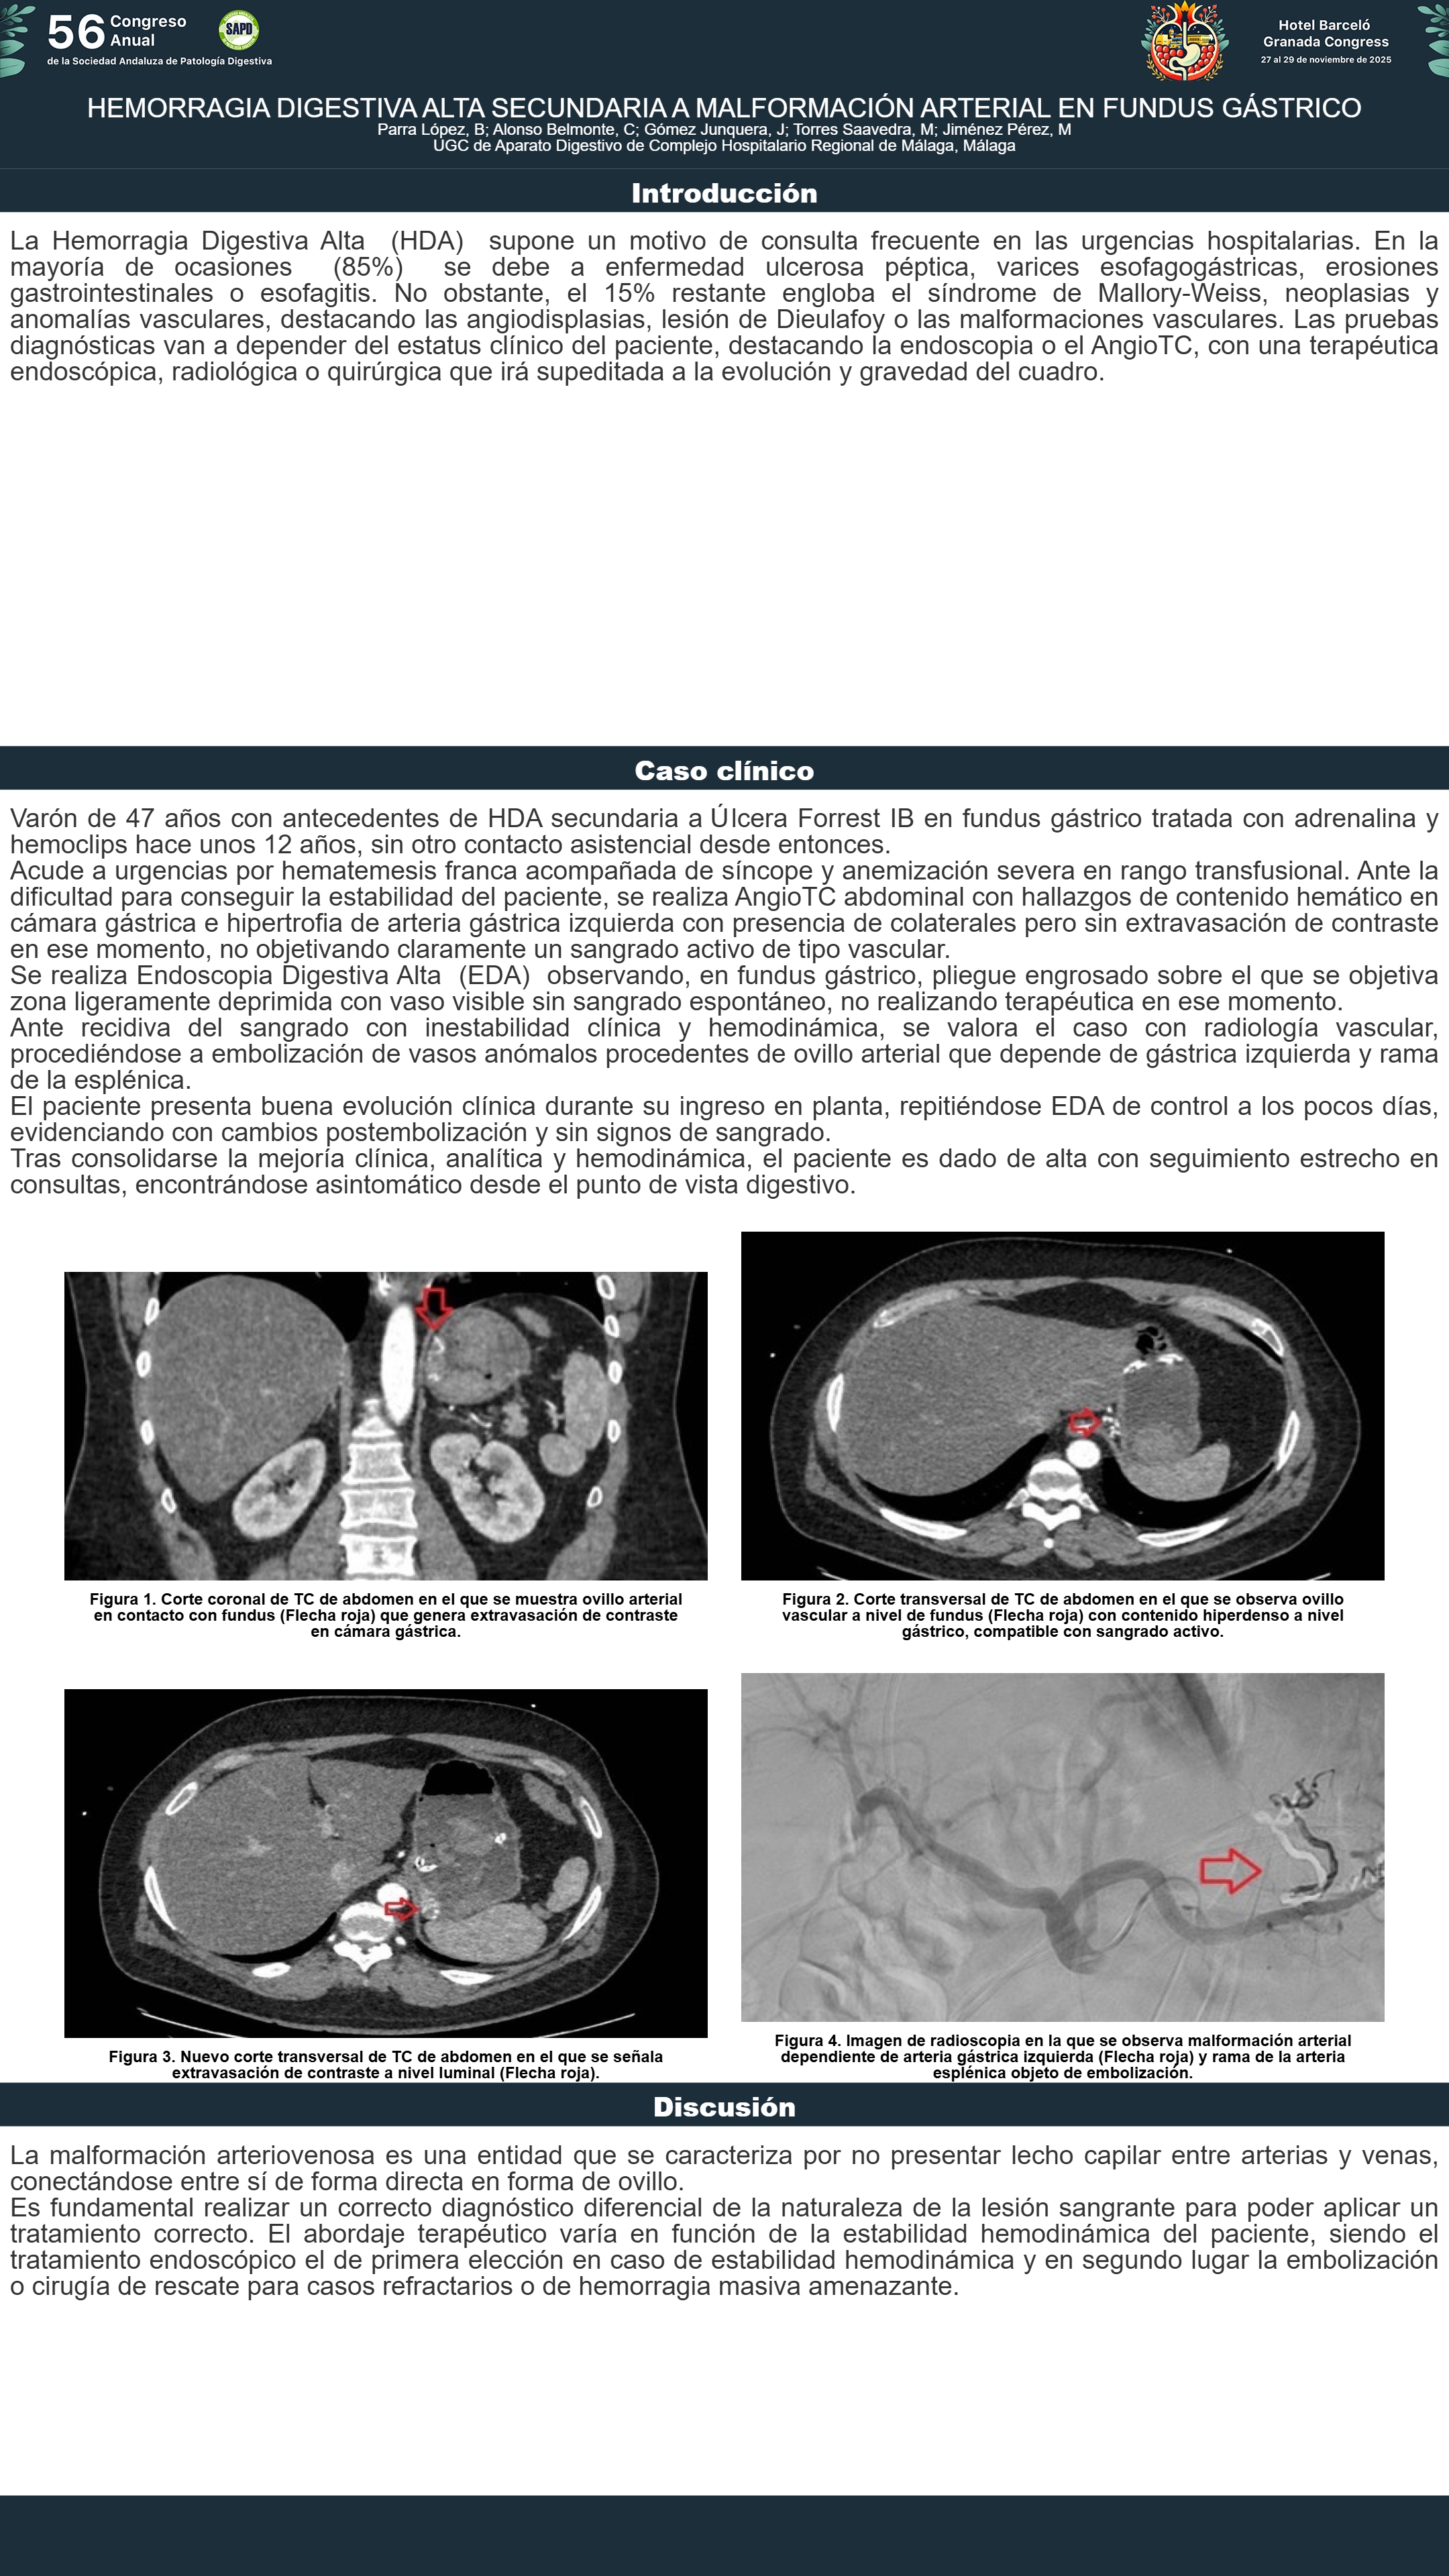

[CP-174] HEMORRAGIA DIGESTIVA ALTA SECUNDARIA A MALFORMACIÓN ARTERIAL EN FUNDUS GÁSTRICO